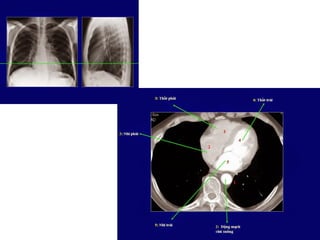

• Xác định rãnh liên thùy  thùy

• Phế quản và động mạch đi vào trung tâm

phân thùy phân thùy

GIẢI PHẪU PHÂN THÙY PHỔI

Đầumũitên:rãnhliên thùybé

Mũi tên:rãnh liênthùylớn